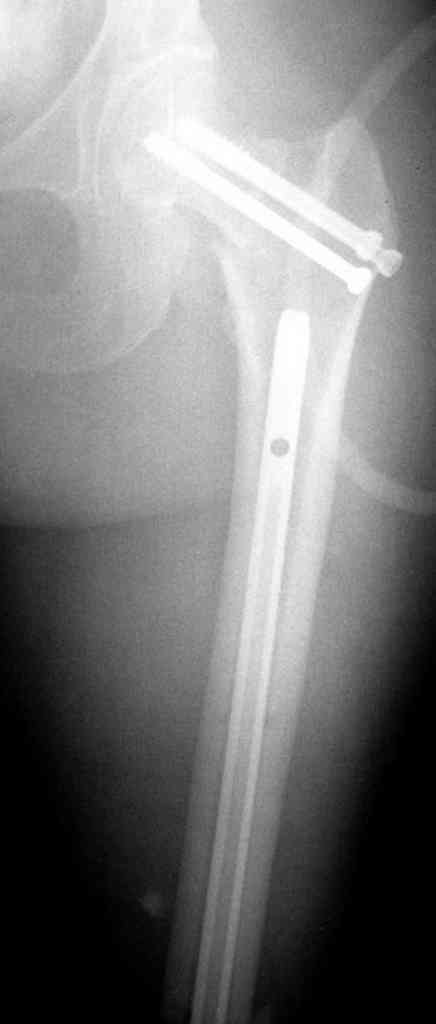

На снимках ложный сустав шейки бедра, несостоятельность фиксации. По положению шурупа можно предсказать ложный сустав, например, если screw backup за кортикальный слой около 15-20 мм, и также изменение угла от первоначального.

№2-3 типичная ошибка несоблюдения концепции параллельности шурупов, нарушение-фиксация поперечным допольнительным шурупом для приближения отломка в результате не сработало метод параллельных шурупов

№4 результат на КТ